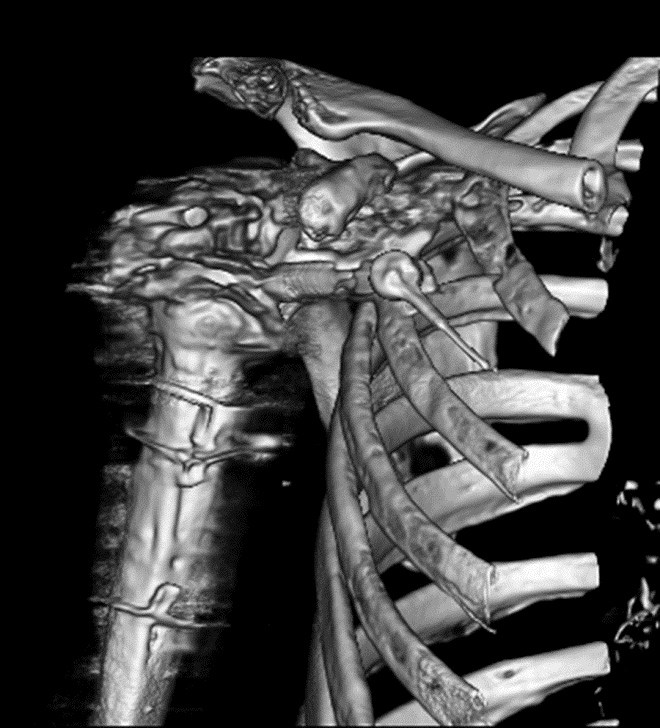

Three-dimensional volume rendering techniques may also be useful to reduce hardware-associated streak artifact (Calhoun, 1999; Fayad, 2009). However, even so, the presence of severe streak artifact may result in rendering of unacceptable streaking limiting the quality and utility of the three-dimensional reconstruction. Given this, three-dimensional volume rendering may be most useful for evaluation of metal hardware rather than adjacent bone (Figure 5).

Figure 5A Figure 5B Figure 6A Figure 6B

3d reconstruction 3d reconstruction Dual energy CT Dual energy CT

Periprosthetic 3D Reconstruction. (A) 3D reconstruction of osseous anatomy surrounding right total shoulder arthroplasty without dual-energy technique demonstrates significant artifact limiting evaluation of hardware and glenohumeral joint. (B) Dual-energy CT 3D reconstruction focused on metallic hardware demonstrates excellent visualization of hardware with metaglene screw fracture (arrow). Dual Energy CT. (A) Axial CT image acquired with dual energy technique demonstrates minimal artifact secondary to sacroiliac joint screws. (B) Coronal multi-planar reformation demonstrates excellent visualization of the osseous anatomy and hardware with further minimization of artifact.